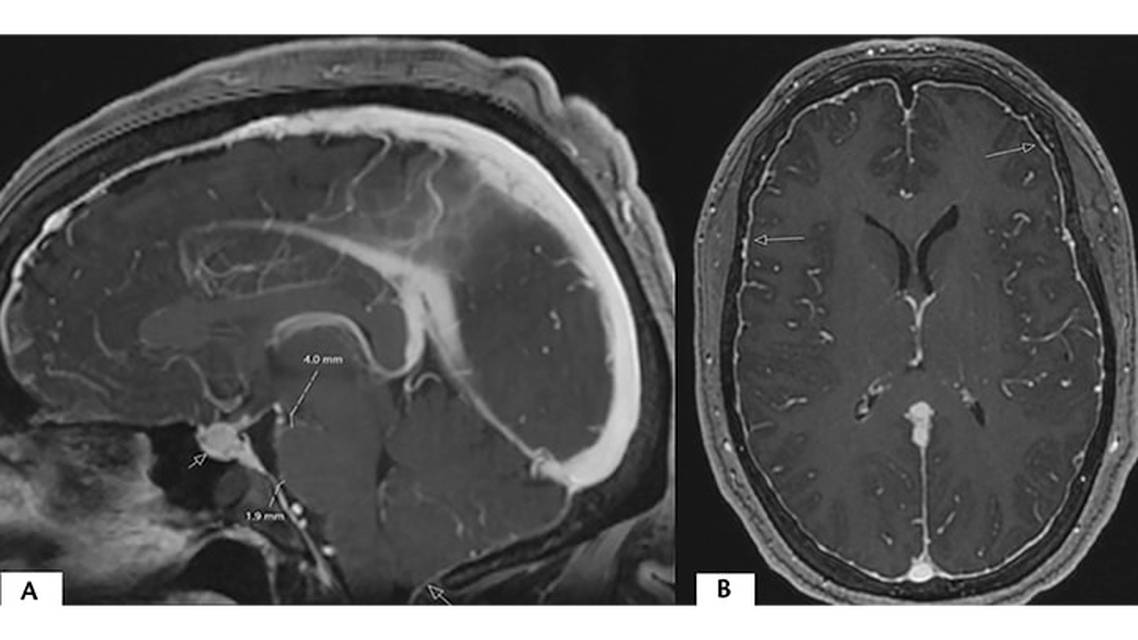

Both qualitative (Table 3) and quantitative measurements of imaging studies can be used in determining the likelihood of SIH.12 Subdural fluid collections can be hygromas and may be bilateral or unilateral. Occasionally, these can be subdural hematomas that have grown large enough to become symptomatic.13 Engorgement of the venous structures may not be self-evident and is best examined in comparison with prior imaging, if available.13 Pituitary hyperemia can appear similar to pituitary hyperplasia or neoplasia.14 Sagging of the brain manifests as brain displacement, often below the foramen magnum appearing similar to a type 1 Chiari malformation.15

Measurement of specific imaging signs can also be useful. The size of the suprasellar cistern, prepontine cistern, and the mamillopontine distance have all been shown to be strongly correlate with the presence of a CSF leak.16,17 Imaging, however, is not the sine qua non of CSF leak diagnosis; a negative or atypical brain MRI may be present, particularly if there has been a lengthy history of leak that can further obscure the diagnostic picture.12,18,19 Emphasizing this point, it was recently reported that 10% of people with orthostatic headache and normal brain and spine imaging using conventional modalities (eg, MRI and CT myelogram) had a surgically fixable CSF-venous fistula (ie, CSF loss directly into paraspinal vein) when lateral decubitus digital subtraction myelography (LDDSM) was used.20 This 10% is comparable to the yield of conventional imaging in this population.21